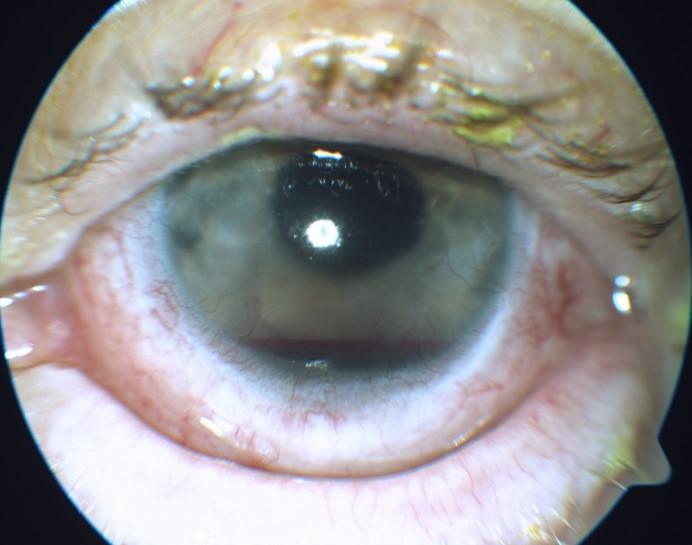

Slit lamp examination OD was remarkable for 2+ meibomian gland disease. Slit lamp examination OS was remarkable for 2+ meibomian gland disease, trace diffuse bulbar conjunctival injection, and trace bulbar conjunctival edema. The cornea had 3+ diffuse edema with guttata and 3 clock hours of pannus and neovascularization (Figure 1). The anterior chamber had a 1-mm tall hyphema (Figure 2) and anterior chamber reaction of 4+ cells and 1-2 flare. Clear and complete visualization of the iris was challenging due to the hyphema obstructing the inferior iris, 3+ corneal edema and 4+ cells and 1-2 flare anterior chamber reaction, making it difficult to completely rule out iris neovascularization. Posterior structures were also difficult to assess due to the corneal edema, hyphema and anterior chamber reaction. Therefore, a B-scan ultrasound was performed. No masses or retinal detachments were detected (Figure 3). Fundus examination and gonioscopy were performed only OD due to the presence of the hyphema OS. No abnormal vessels in the angles, angle neovascularization or other abnormalities were noted OD.

![]() Figure 3. B-scan ultrasound of the left eye on the day of patient’s initial presentation to clinic. Note the absence of retinal detachment or masses. Click to enlarge |